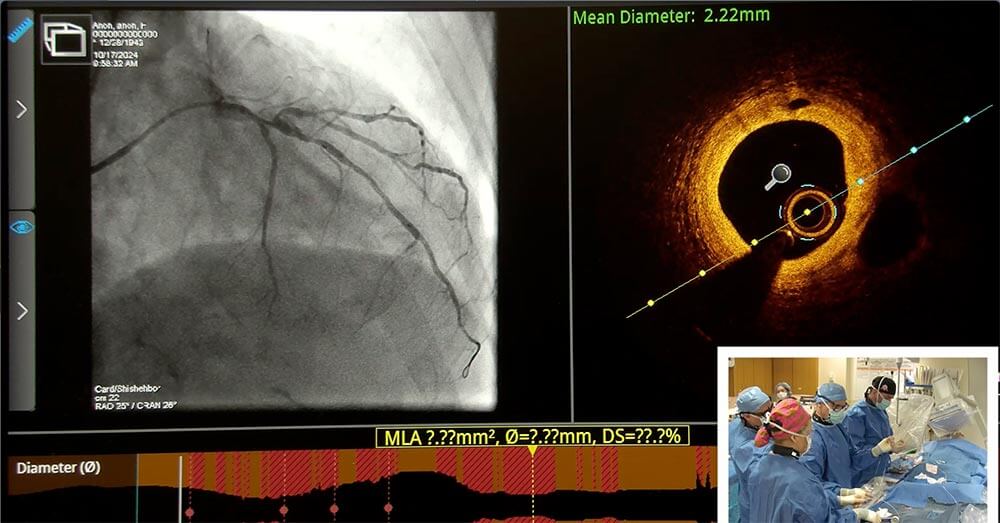

- Stent optimization techniques including intracoronary imaging